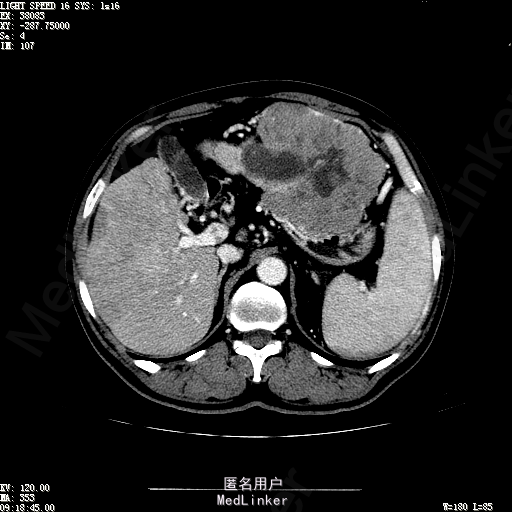

查体:生命体征平稳,神志清晰,发育正常,营养中等,体位自如,表情安静,无面容,配合检查合作。皮肤粘膜颜色正常,腹型平坦,无腹壁静脉曲张,未见胃肠型及蠕动波,无瘢痕,脐部正常。触诊:无压痛,无反跳痛,无腹肌紧张,无腹部包块。肝未触及,Murphy征阴性,脾未触及,肾未触及,无移动性浊音。 化验回报:血细胞分析(五分类):*白细胞计数 4.6 10^9/L、红细胞计数 4.27 10^12/L、血小板计数 100.0 10^9/L、血红蛋白 145 g/L、中性粒细胞百分比 68.6 %,*葡萄糖测定:葡萄糖 5.99 mmol/L,血清离子测定:*钾 4.46 mmol/L、钠 143.5 mmol/L,肾功能检测:*尿素 6.86 mmol/L、肌酐 84.2 umol/L,凝血五项:凝血酶原时间 10.7 秒、凝血酶原百分活动度 93.3 %,乙肝六项:乙型肝炎病毒表面抗原 阳性(+) 、乙型肝炎病毒e抗体 阳性(+) 、乙型肝炎病毒核心抗体 阳性(+) ,甲胎蛋白测定:甲胎蛋白 7146.00 ng/mL,ALT23U/L,AST42U/L CT检查如下图

诊断:乙肝肝硬化 静止性 代偿期 原发性肝癌 2型糖尿病 高血压病 下肢动脉闭塞征 诊断依据:1.有明确乙肝肝硬化病史 2.肝区隐痛,于外院发现肝占位,我院诊断肝癌,已行TACE治疗 3.查体:有肝掌 4.既往影像学提示肝内占位 处置:血管介入治疗:患者平卧位,以左侧肘窝为中心常规消毒、铺巾、利多卡因局麻。超声引导下,于肘横纹上方1厘米处确定皮肤穿刺点,改良Seldinger法逆行穿刺左侧肱动脉成功,置入5F血管鞘。沿导丝送入Cobra C2导管,送入降主动脉,将管头送入腹腔干,进一步送至肝固有动脉。造影见肝内广泛弥漫肿瘤染色,以右叶为主。以微导管超选肝右动脉,造影明确为肿瘤供血动脉,注入碘化油5毫升。退出微导管,经C2管注入奥沙利铂100毫克。退出C2管。拔出血管鞘,局部压迫10分钟。加压包扎。患者送返病房。